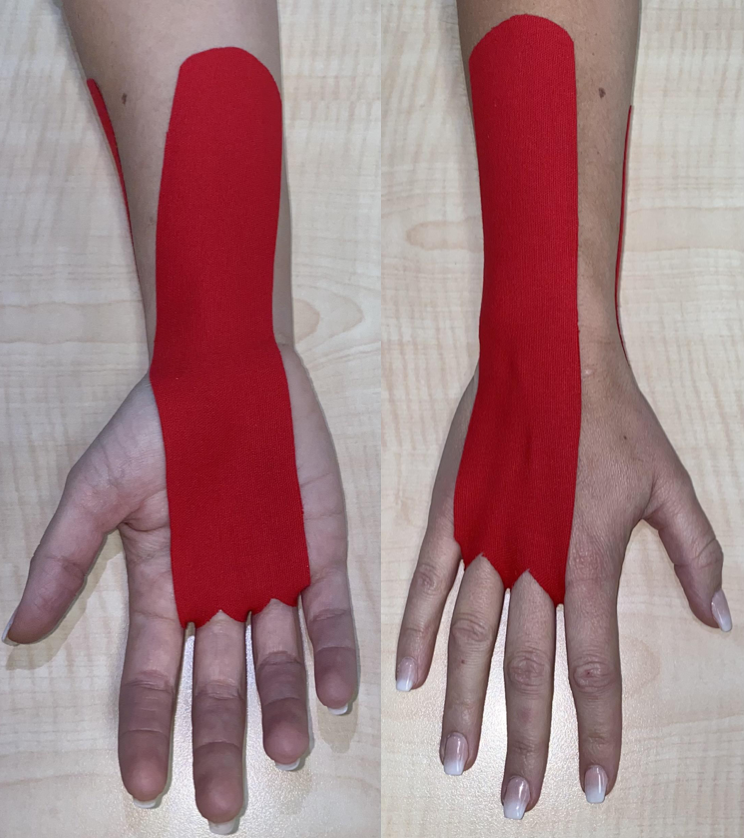

Rotator Cuff Pain: K Tape + Rehab Short-Term Effects

Nguyen, T. N. A., Nguyen, N. H., Vu, D. K., & Cu, L. T. N. (2025). Short-term effects ofKinesiotaping combined with a rehabilitation program for ...